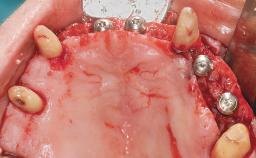

Immediate Loading of Eight Implants in the Maxilla and Six Implants in the Mandible and Final Restoration with Three-Unit and Four-Unit FDPs

Extensive scientific evidence has confirmed that immediately loaded implants with fixed full-arch provisional restorations can osseointegrate with success rates similar to conventionally or delayed loaded implants. A number of immediate-provisionalization techniques for edentulous jaws have been described. Some protocols differ when it comes to prefabricated provisional templates versus complete denture conversion; intrasurgical impressions versus direct relining; and cemented versus screw-retained provisional restorations. In this context, complete-denture conversion has been proposed for either intrasurgical impressions or direct relining. Another possibility is the utilization of a prefabricated provisional to be adapted either in the mouth (by direct relining) or in the laboratory (on a working model obtained from an intrasurgical impression).

Surgical SAC classification

SAC Level Complex

Defining Characteristics Fully edentulous upper jaw to be rehabilitated with four or more implants

Modality 6+ implants with immediate loading

Bone Volume Horizontally and vertically sufficient

Esthetic Risk High

Complexity High

Risk of Complications High